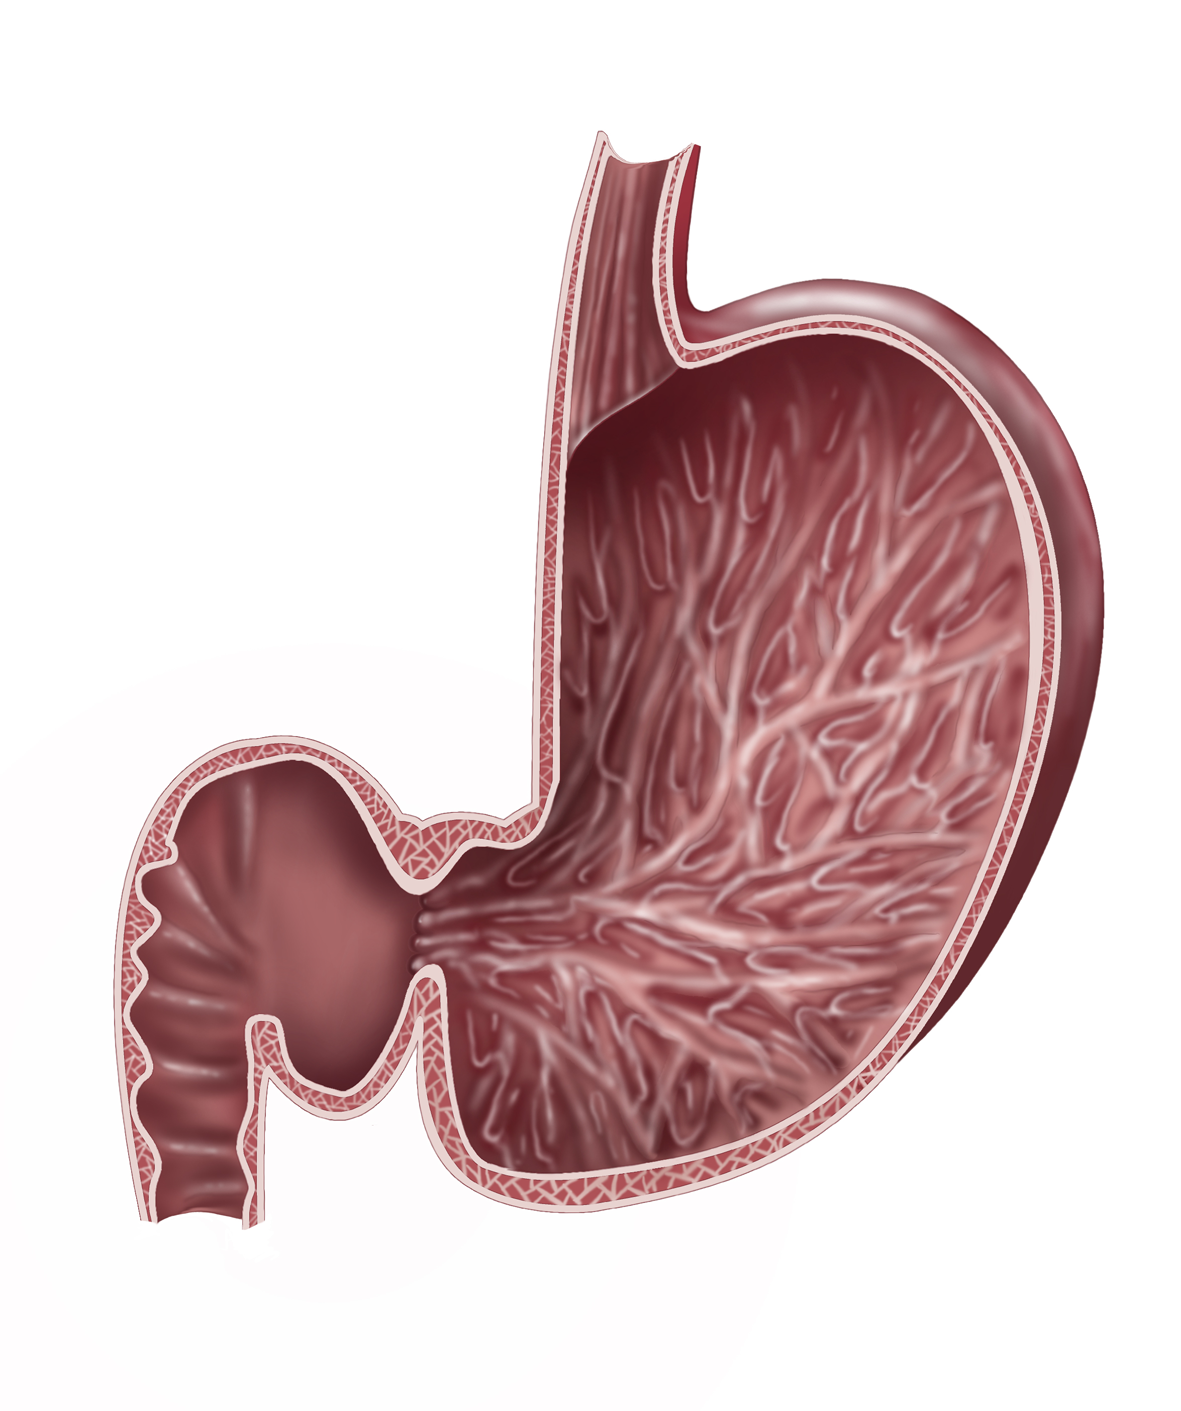

Herzlich willkommen! Ich bin Ihre Expertin für medizinische Illustrationen und kreative Kinderbuch-Illustrationen. Mit einem Auge für wissenschaftliche Genauigkeit und einer Liebe zur Gestaltung kindgerechter Erzählwelten schaffe ich Bilder, die informieren und begeistern. Entdecken Sie mein Portfolio und lassen Sie sich von meiner Arbeit überzeugen!